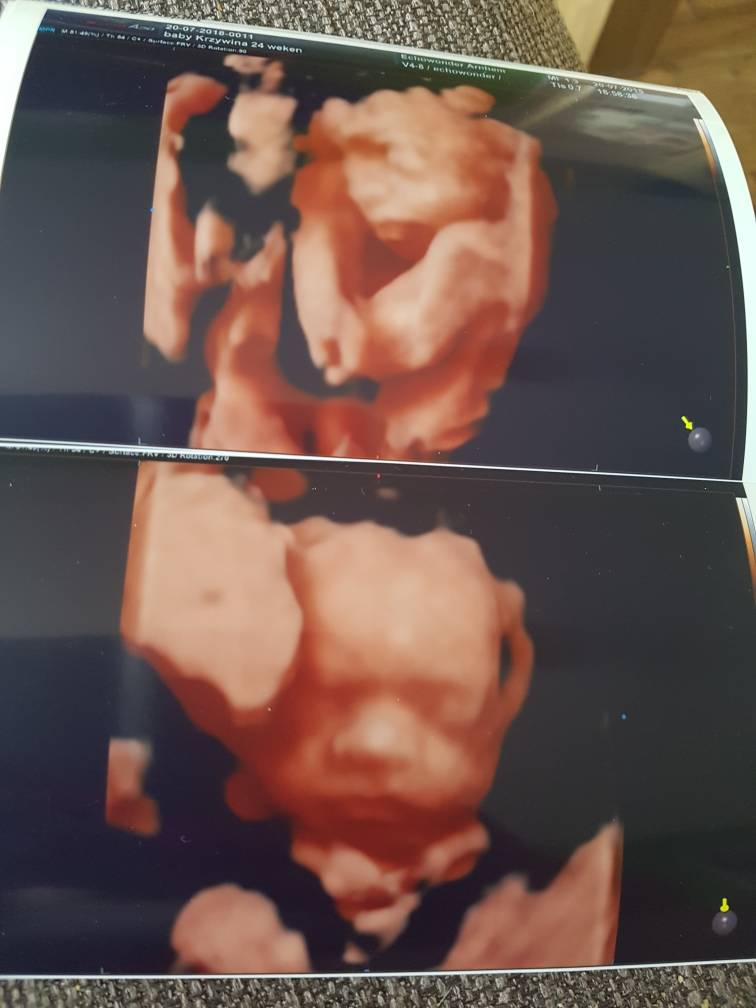

Jejku jaka śliczna.My juz po dzieciaki zachwycone 100 % dziewczynka juz wrzucam zdjeciaZobacz załącznik 879662

My juz po dzieciaki zachwycone 100 % dziewczynka juz wrzucam zdjeciaZobacz załącznik 879662